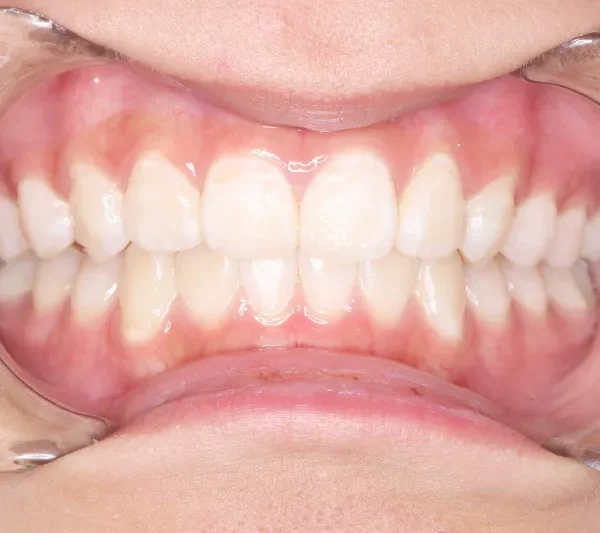

治療回数43回、7年4ヶ月の治療期間で矯正治療を終了しました。

主訴が改善され、ご満足頂きました。

治療終了後